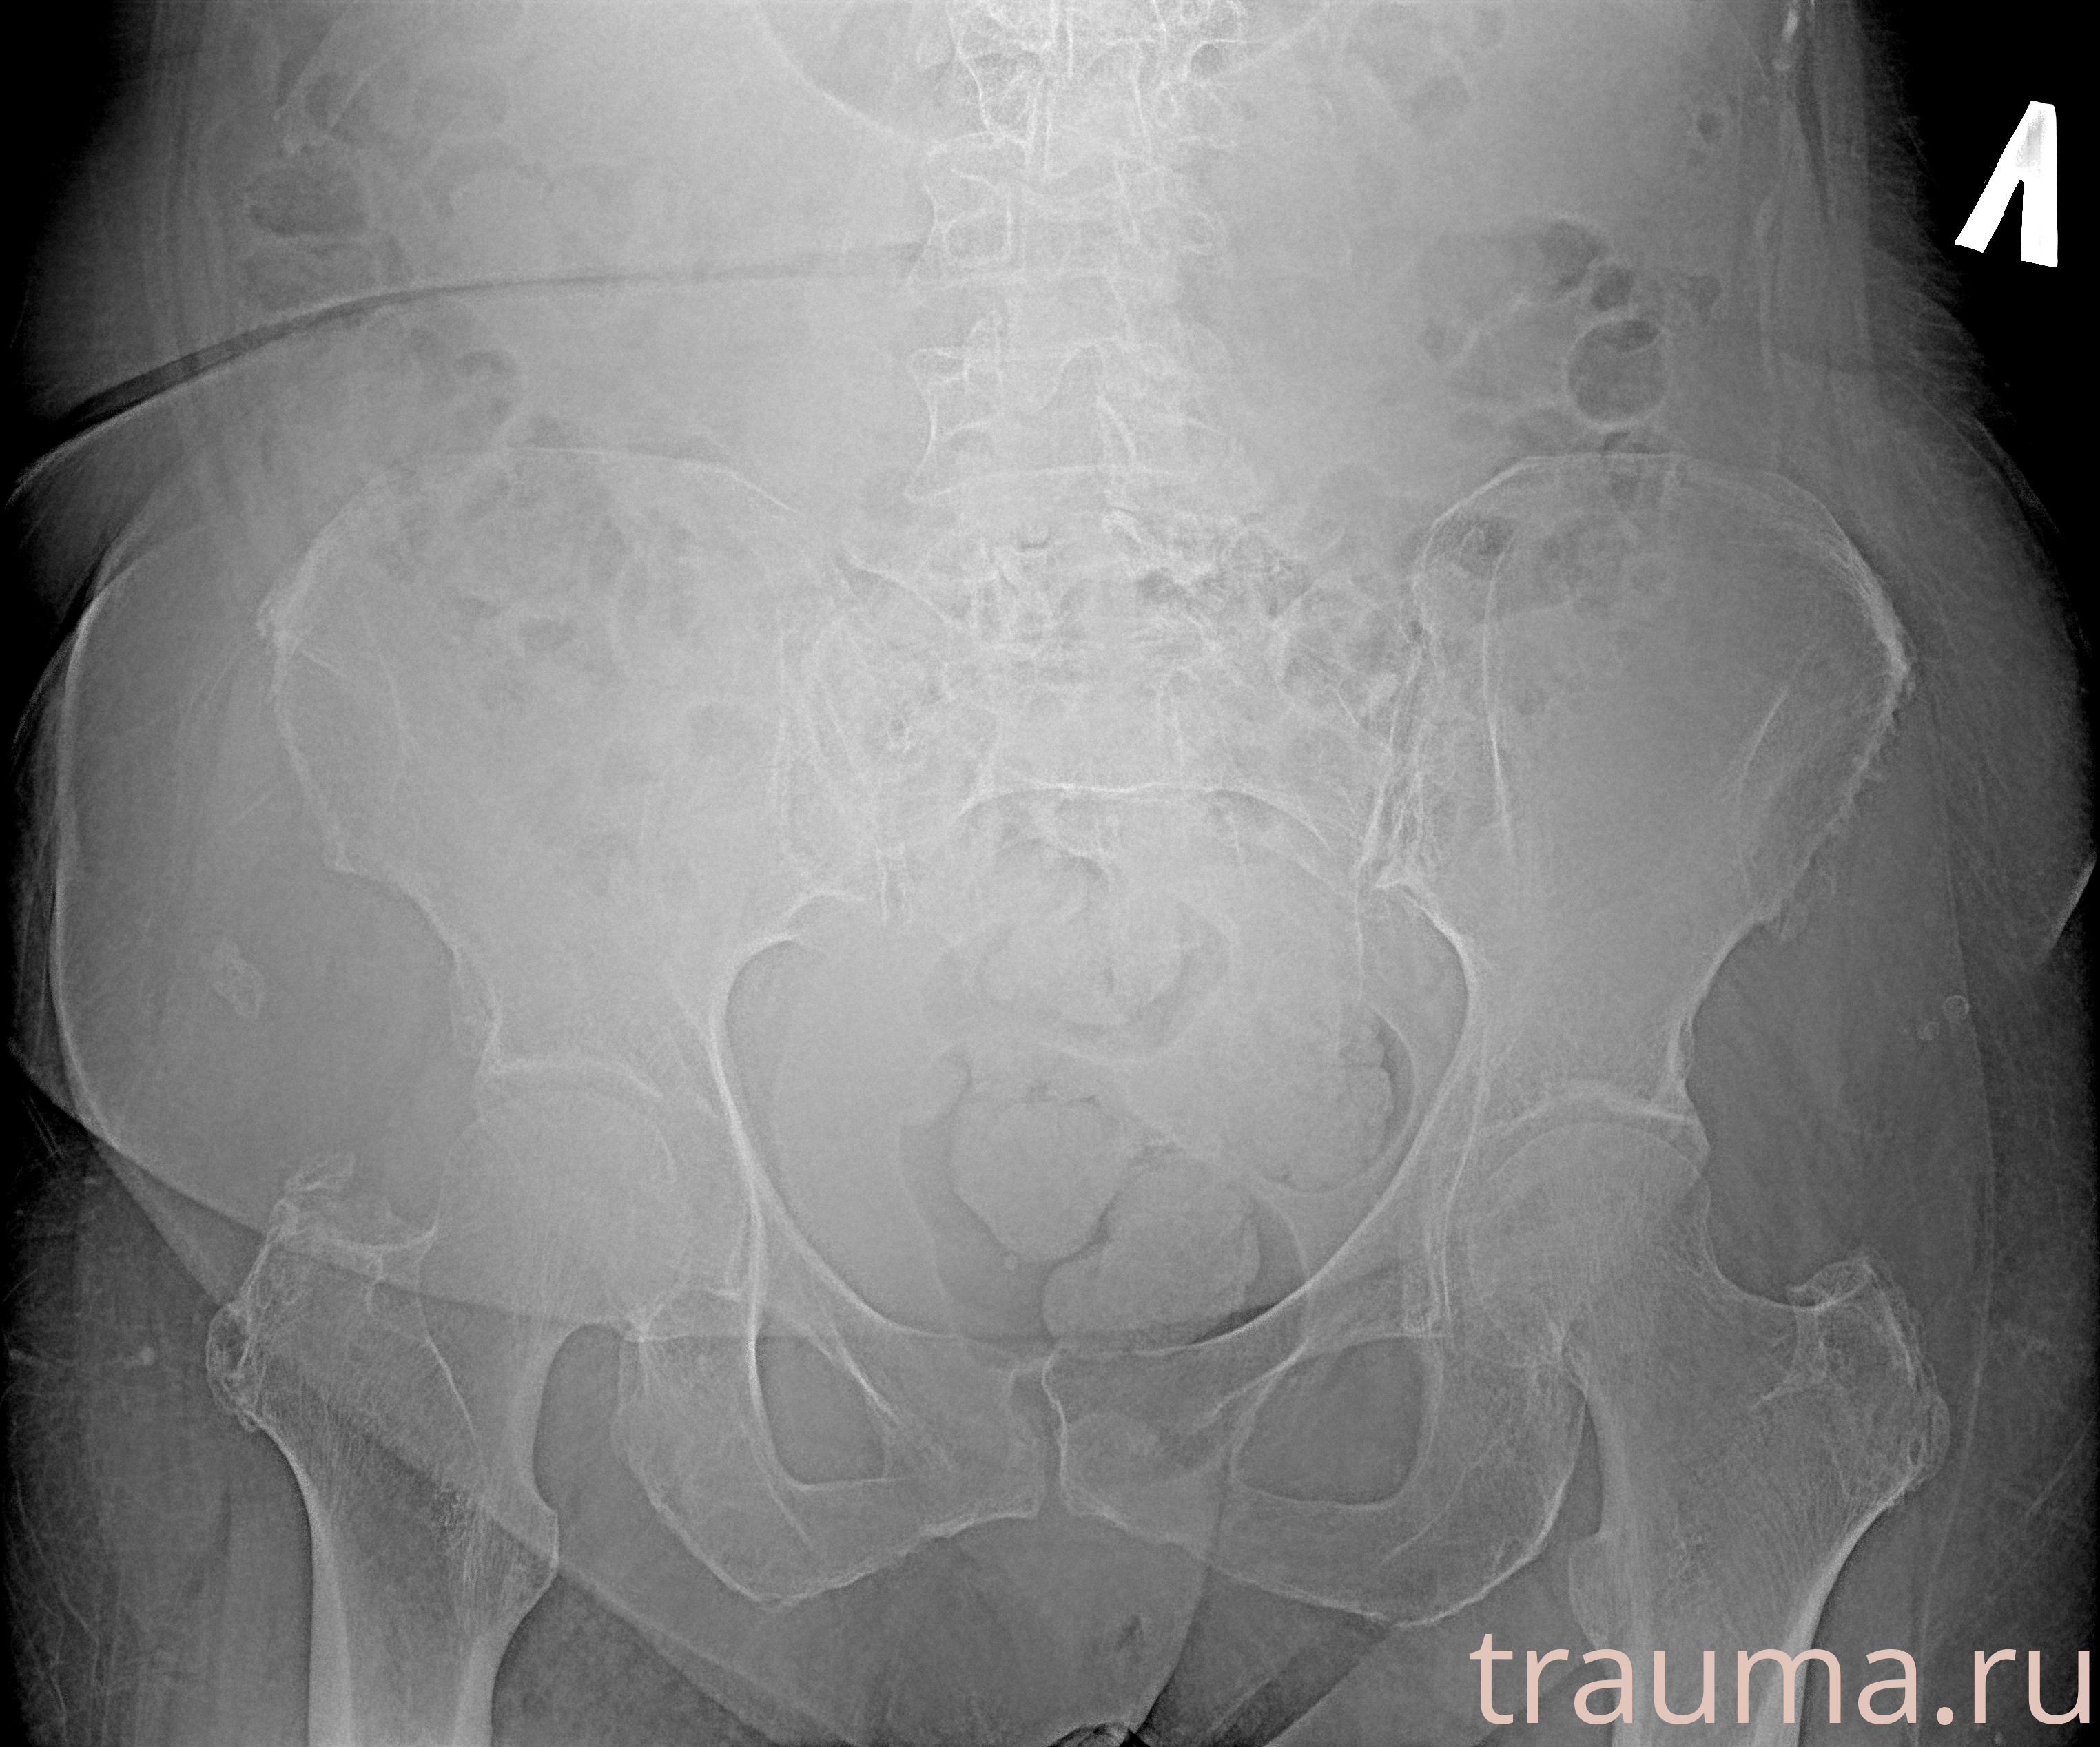

Рентгенограммы

Рентген на дому: по вашему адресу приезжает врач-рентгенолог, травматолог-ортопед с мобильным рентгеновским аппаратом, проводит диагностику травмы или заболевания, делает необходимые рентгенограммы, дает рекомендации по дальнейшему лечению. Получить качественные снимки в домашних условиях возможно благодаря уникальной методике, разработанной МосРентген Центром для института  Склифосовского